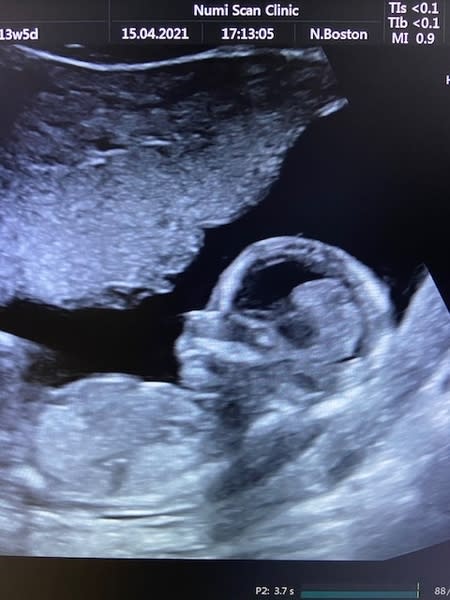

Numi Scan Stansted, offer a variety of baby scanning packages to suit all stages of your pregnancy. Whether you're looking for a wellbeing scan, reassurance scan or a 4D scan, you can expect a 5 star service!

Our scan packages are aimed at providing you with essential information about the well-being of your baby, as well as giving you the opportunity to bond with your baby in a luxurious setting.

Whether you're looking for gender confirmation, reassurance or the chance to bond with your baby with a 4D scan, we will make it a special occasion for you and your family.